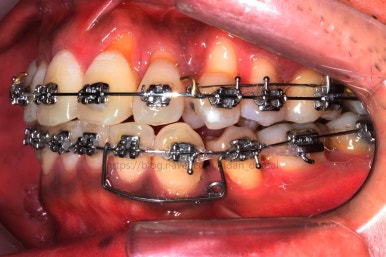

치료 시작 3개월째의 모습입니다.

서서히 가지런해지는 느낌이 드시나요?

화살표를 보면 작은 어금니 하나가 아래로 꺼져있는데, 이 녀석 때문에 애를 먹었네요. 훨씬 치료가 빨리 끝날 수 있었는데 이 치아가 워낙 잘 안움직이는 바람에 2년 개월정도로 치료기간이 많이 걸린 편이었어요.

치료 8개월째의 모습입니다.

이제 얼핏 보면 매우 가지런해졌어요. 이 뽑은 자리도 많이 남지 않았고 왼쪽 위 송곳니가 없지만 그리 표시도 많이 나지 않네요.

대신 위쪽 아래 작은 어금니가 애를 먹이고 있어요. 낚시줄처럼 부여매고 끌어올리는게 보이실거에요.